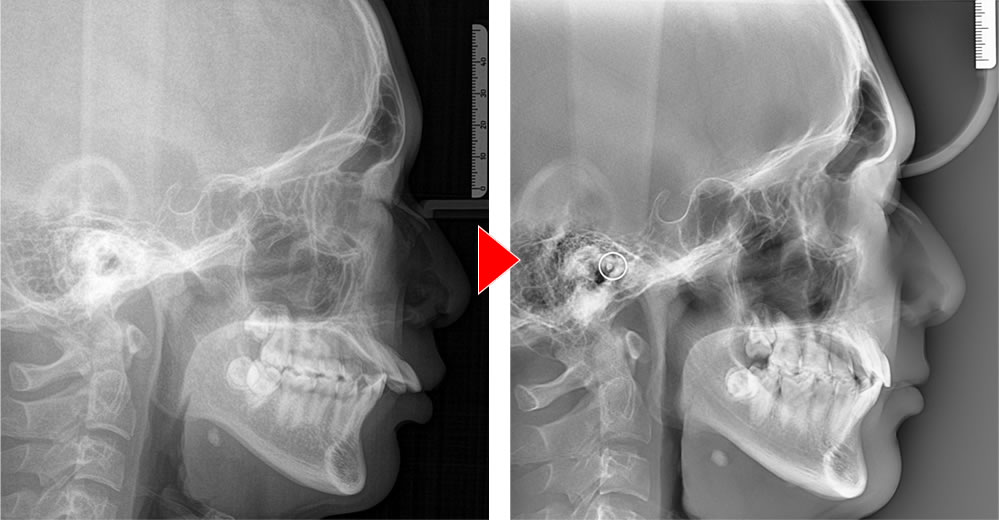

矯正治療前後のレントゲン画像

こちらは治療前と治療後のレントゲンの比較になります。前歯が引っ込み、スッキリとした印象になりました。